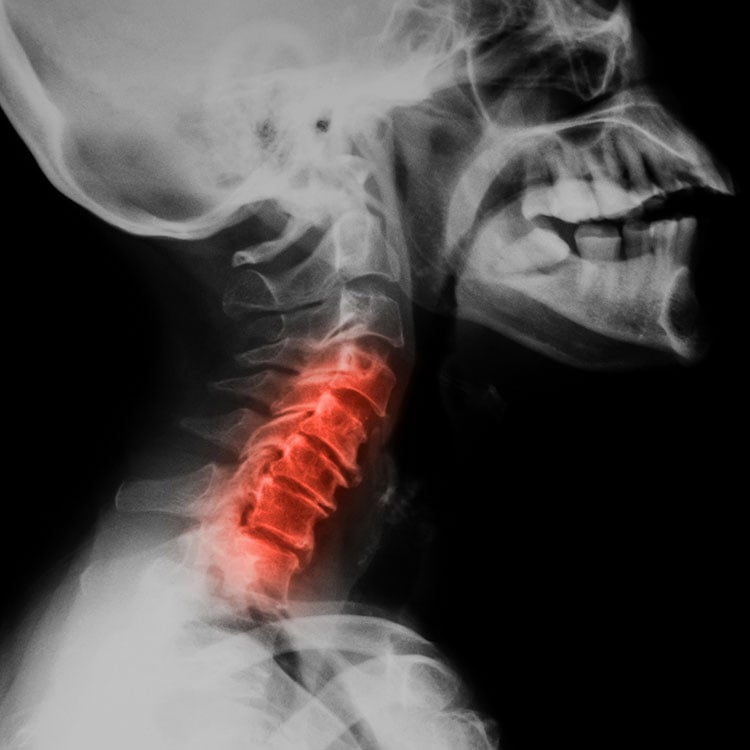

Cervical Spine Injuries in Sports Hughston Clinic Side Effects Of Cervical Nerve Ablation One common side effect of cervical radiofrequency ablation is temporary soreness or discomfort at the site of the treatment. Burning and/or hypersensitivity over the injection site; Numbness and/or tingling over the injection site; What are the side effects and potential risks of radiofrequency ablation? Radiofrequency ablation for neck pain is associated with several side effects, which include: Facet rfa is. Side Effects Of Cervical Nerve Ablation.